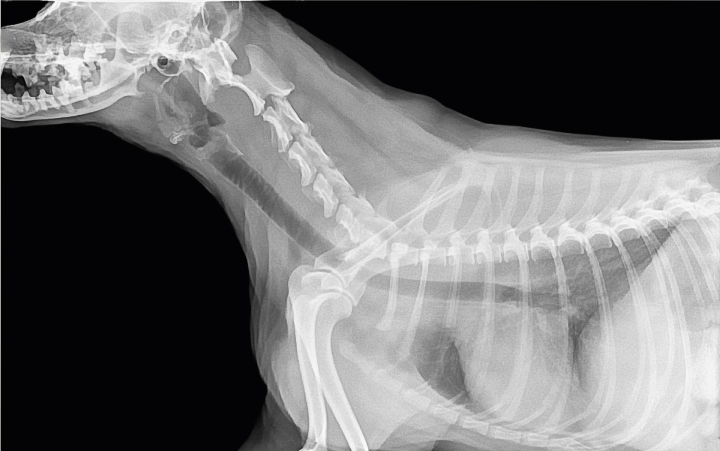

Estudio Radiográfico con contraste

Un estudio radiográfico con contraste es una técnica avanzada de imagenología utilizada para obtener una visión más detallada de las estructuras internas de su mascota. A diferencia de las radiografías convencionales, que muestran imágenes generales de huesos y tejidos, el uso de contraste permite resaltar y diferenciar estructuras específicas dentro del cuerpo.

- Permite una visualización detallada de estructuras internas y procesos patológicos, mejorando la precisión del diagnóstico

- Ayuda a evaluar la función de órganos y sistemas, como el tracto gastrointestinal, el sistema urinario y el sistema cardiovascular.

- Facilita la planificación de tratamientos más específicos y efectivos al proporcionar una visión clara de la condición de su mascota..